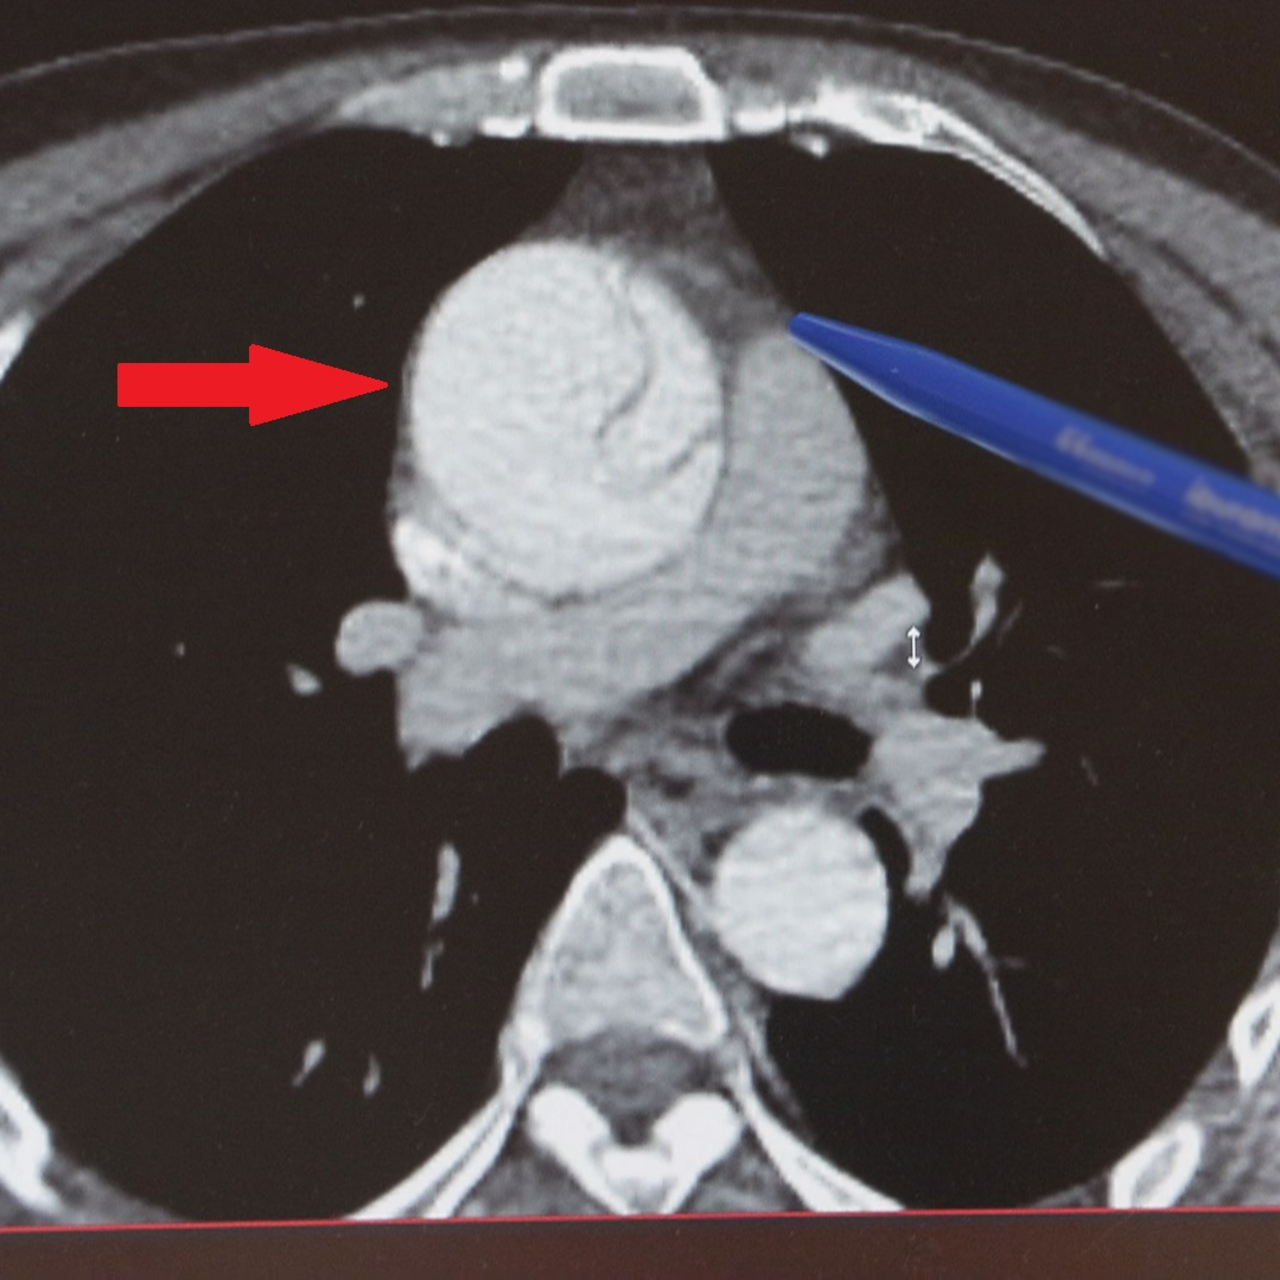

İstanbul'da 41 yaşındaki Mustafa Turan, göğsünden karnına doğru aniden başlayan şiddetli bir ağrı ile acile kaldırıldı. Tetkikleri normal çıktı, mide ağrısı sanılıp eve gönderildi. Sonraki 24 saat boyunca ağrısı hiç azalmadı, gece 02:00 sularında Göztepe Süleyman Yalçın Şehir Hastanesi aciline gitti ve nöbetçi doktorun dikkati sayesinde yapılan ileri tetkiklerle, aort damarında anevrizmaya (baloncuk) bağlı yırtık olduğu tespit edildi. Acilen ameliyata alınan Turan, şans eseri ölümden döndü. Kalp Damar Cerrahisi Klinik Şefi Prof. Dr. Ebuzer Aydın, risk grubunda olanların düzenli kontrol yaptırması gerektiğini söyledi ve "Yırtığa bağlı acil ameliyatla, planlı ameliyatlar arasında ölüm riski açısından 4-5 kat fark var" dedi